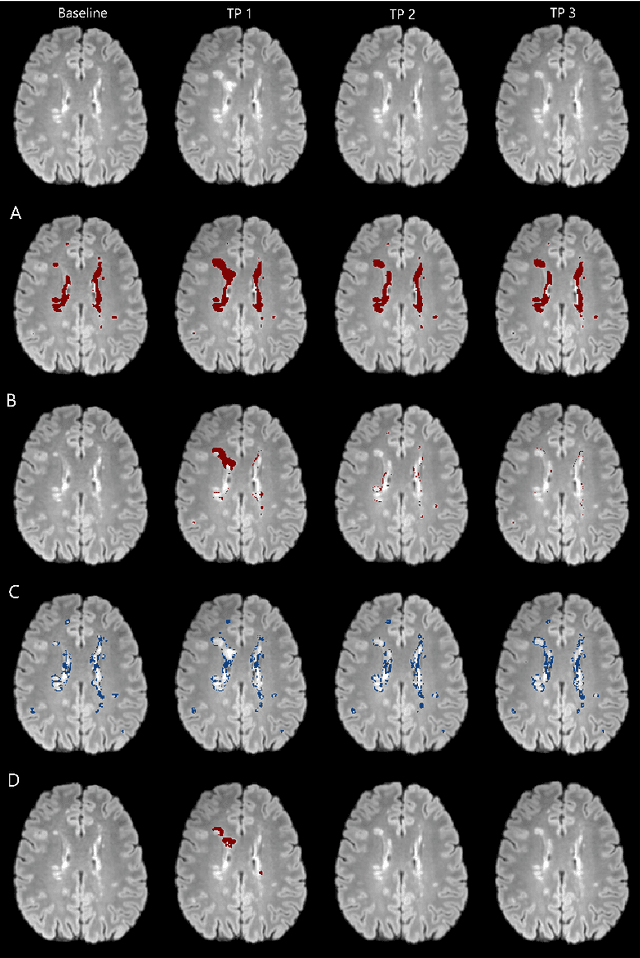

Abstract:The detection of new or enlarged white-matter lesions in multiple sclerosis is a vital task in the monitoring of patients undergoing disease-modifying treatment for multiple sclerosis. However, the definition of 'new or enlarged' is not fixed, and it is known that lesion-counting is highly subjective, with high degree of inter- and intra-rater variability. Automated methods for lesion quantification hold the potential to make the detection of new and enlarged lesions consistent and repeatable. However, the majority of lesion segmentation algorithms are not evaluated for their ability to separate progressive from stable patients, despite this being a pressing clinical use-case. In this paper we show that change in volumetric measurements of lesion load alone is not a good method for performing this separation, even for highly performing segmentation methods. Instead, we propose a method for identifying lesion changes of high certainty, and establish on a dataset of longitudinal multiple sclerosis cases that this method is able to separate progressive from stable timepoints with a very high level of discrimination (AUC = 0.99), while changes in lesion volume are much less able to perform this separation (AUC = 0.71). Validation of the method on a second external dataset confirms that the method is able to generalize beyond the setting in which it was trained, achieving an accuracy of 83% in separating stable and progressive timepoints. Both lesion volume and count have previously been shown to be strong predictors of disease course across a population. However, we demonstrate that for individual patients, changes in these measures are not an adequate means of establishing no evidence of disease activity. Meanwhile, directly detecting tissue which changes, with high confidence, from non-lesion to lesion is a feasible methodology for identifying radiologically active patients.